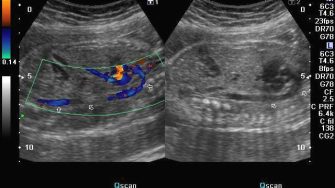

• Application of the first non-invasive bedside tool for determination of vascularity / perfusion (three-dimensional fractional moving blood volume or 3D-FMBV that our team invented).

• Developed the first non-invasive technique for measurement of perfusion using ultrasound (3D-FMBV).

• 2022 funding from the Stillbirth Foundation of Australia for a pilot study looking at 3D-FMBV in prediction of the ‘at-risk’ fetus for stillbirth or intrapartum distress.

Sudden loss of the baby’s heartbeat (stillbirth) is one of the most devastating things that can happen to a family. We know that many babies that pass away in utero have problems with the blood flow in their placenta. We also know that when ‘stressed’ babies can choose where their blood flows (to the brain and other essential organs). We have developed a new way to evaluate normal 3D ultrasound volumes and want to see if we can predict babies at risk.​